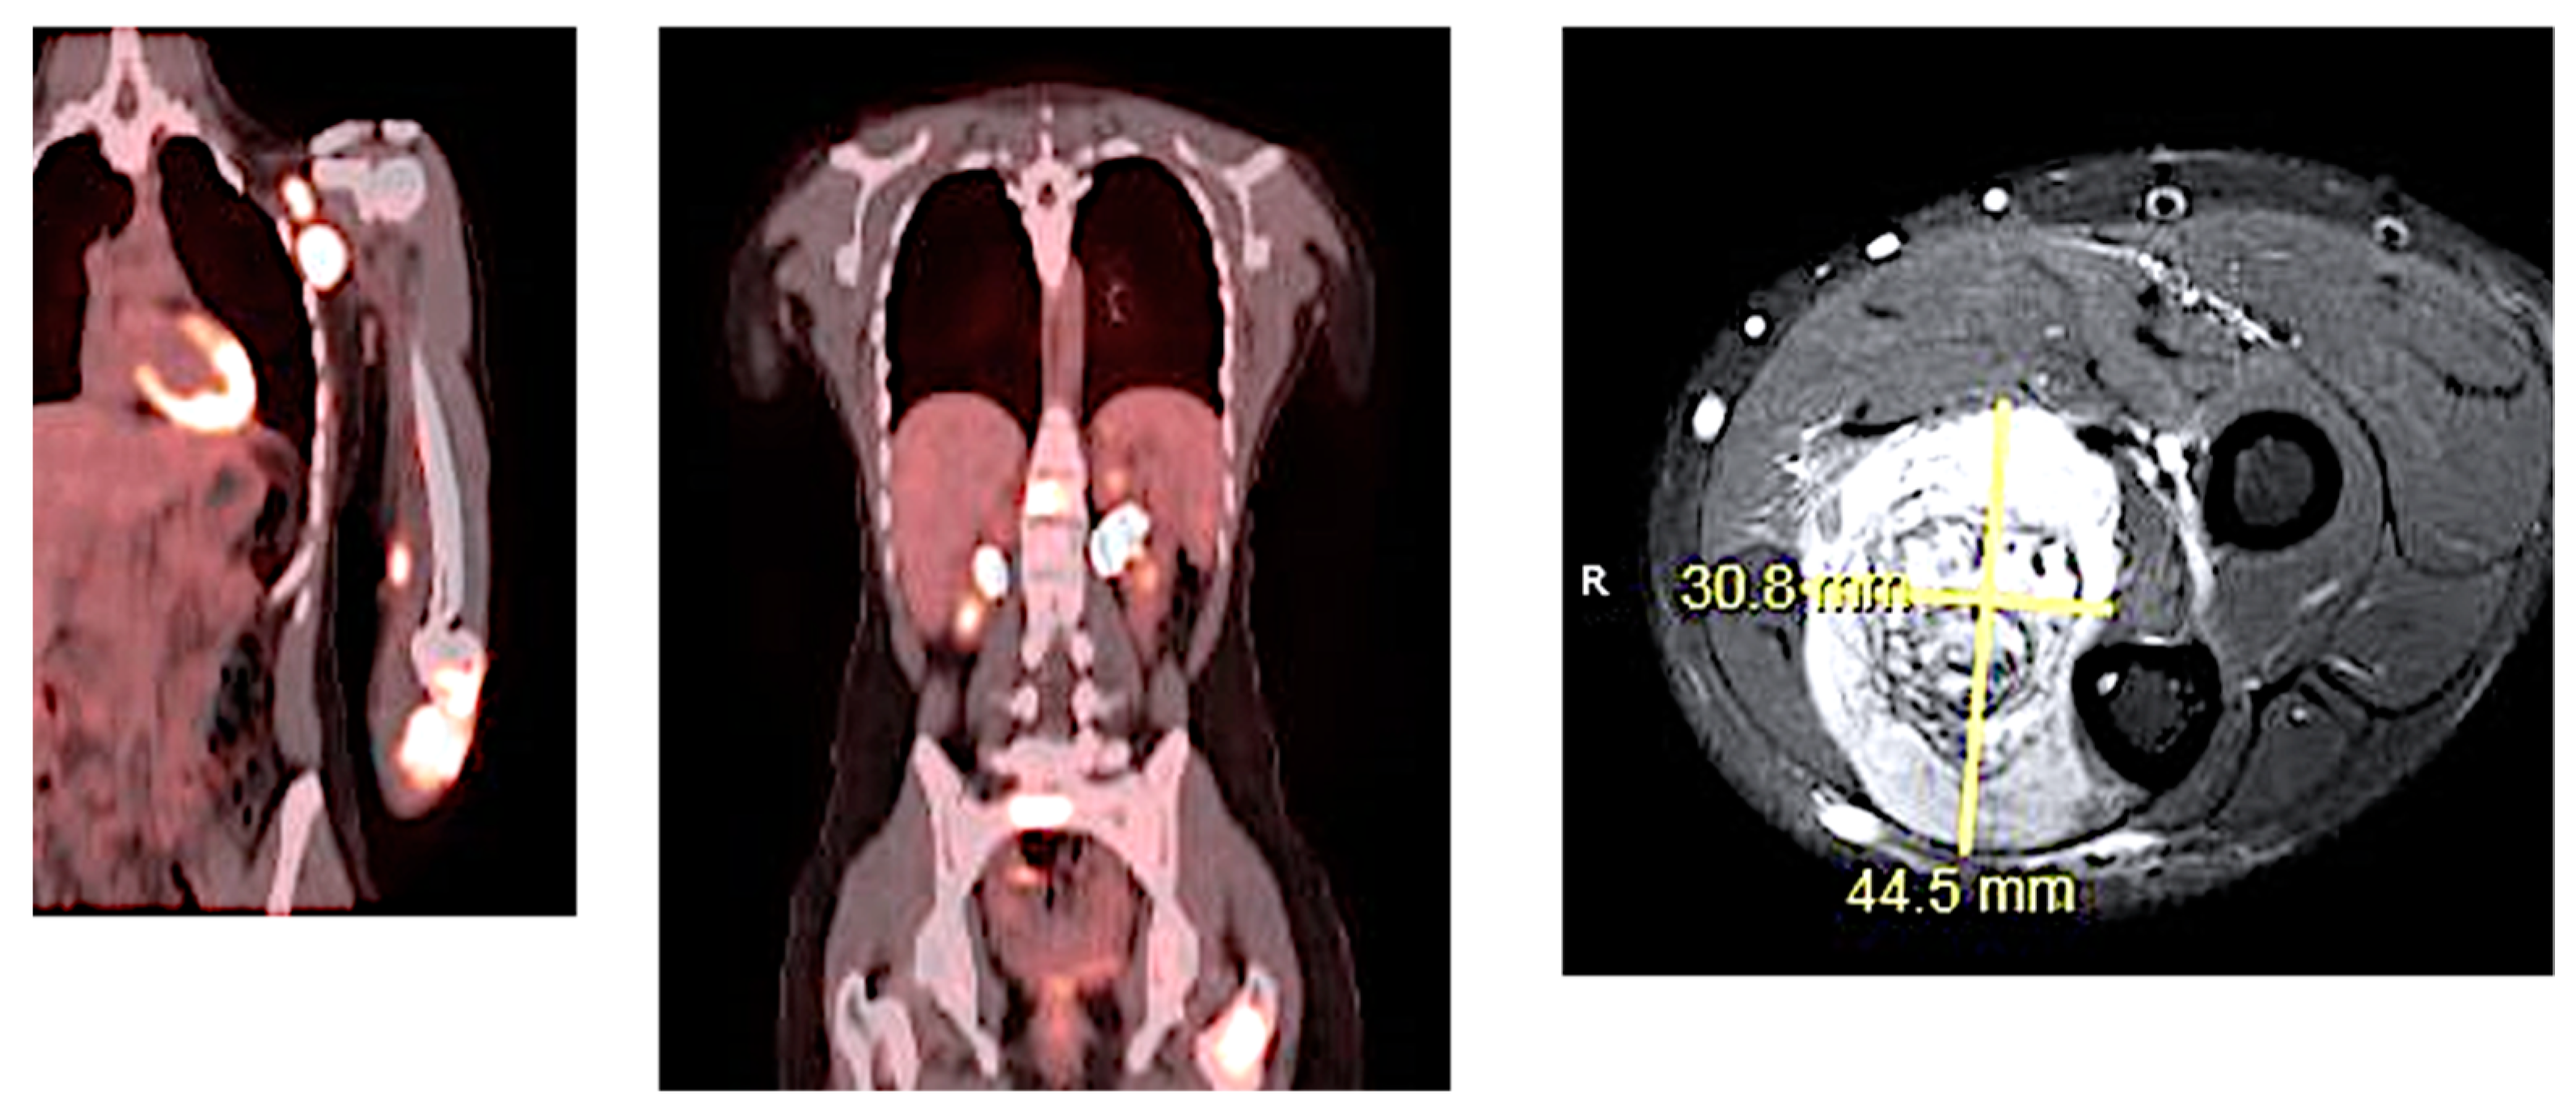

3. Presentation

4. Assessment

14. Assessment